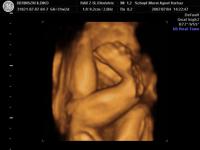

Szóval tegnap voltunk dokinál, méhszáj zárt, minden rendben, Máté pedig szép ütemben fejlődik. Óriásbaba nem lesz, de nem is baj, végülis valahogy elő is kell bújnia egy olyan kisebb kiszerelésű testből, mint az enyém. Ellenben rendezkedik odabent rendesen, meg feszít ezerrel. Élvezem nagyon, kivéve, mikor boxolja a hólyagomat. Meg van egy pont, amit mindig nyom, na az már kezd elég érzékennyé válni.

Aminek örülök: már több, mint 2 hete fejvégű. Remélem, így is marad. (Mellesleg lehet, hogy mégis forgolódik valahogy, mert elég amorf néha a pocim). Keményedések is vannak egyre sűrűbben, de általában csak 1-2 percig tartanak.